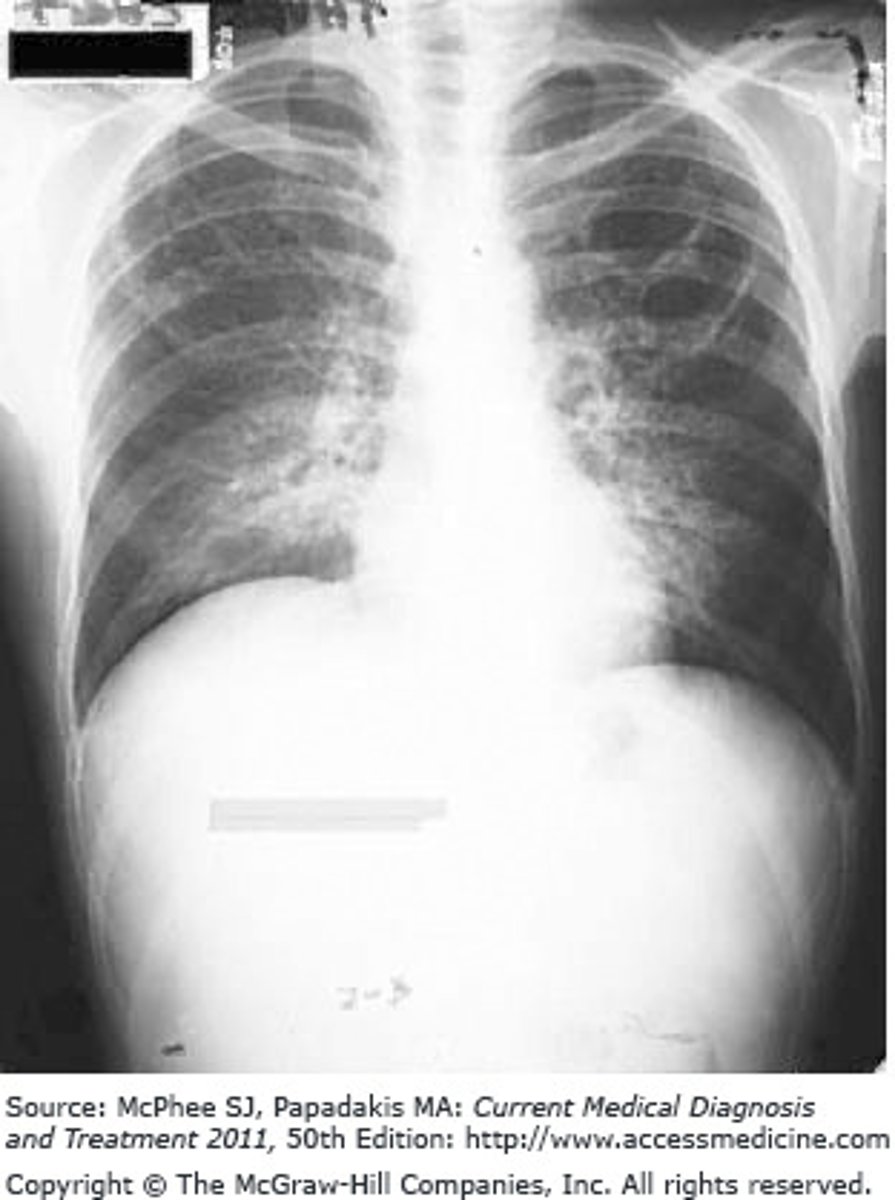

What is the radiographic pattern of a pneumonia that is caused by Pneumocystosis jiroveci in an HIV patient?

The Correct Answer is: D

The presentation of diffuse interstitial infiltrates is what differentiates the patient from a typical pneumonia patient, including the presentation of the history, followed by the chest x-ray results.